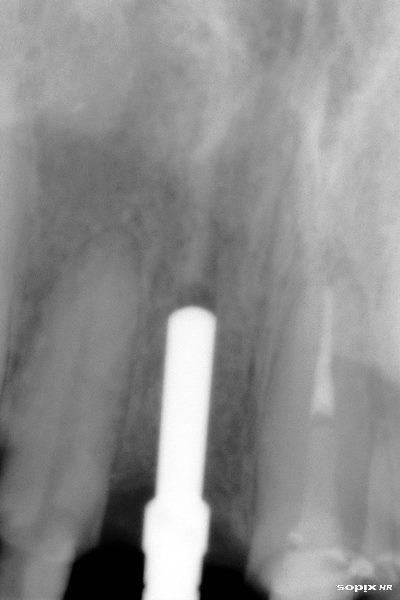

Se coloca poste de impresión

Vista oclusal previa impresión